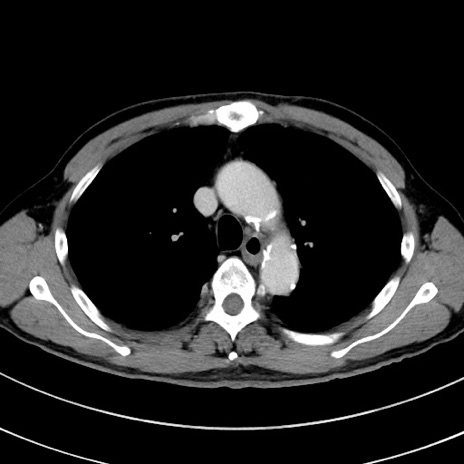

症例8(横断像)

【症例】 60歳代男性

【主訴】 黒色吐物

【現病歴】 4日前から嘔気自覚、2日前の朝食後にも嘔気あり、自分で手で嘔吐反射起こし嘔吐したところ血が混ざっていたため受診。

【既往歴】 5年前汎発性腹膜炎を伴う急性虫垂炎で手術、高血圧、前立腺肥大症、高脂血症

【身体所見】 腹部正中に手術癩痕あり 腹部平坦・軟圧痛なし膨満感あり

【データ】WBC 8400、CRP 4.54